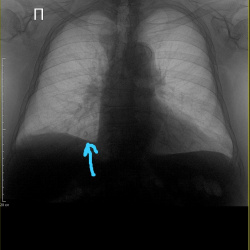

Здравствуйте, женщина 73 года, снимок перед госпитализацией по поводу диабета, лёжа, жалоб со стороны лёгких нет. В нижнем отделе левого лёгкого тень, в данных пациентки нашёл что перенесла 2-х...